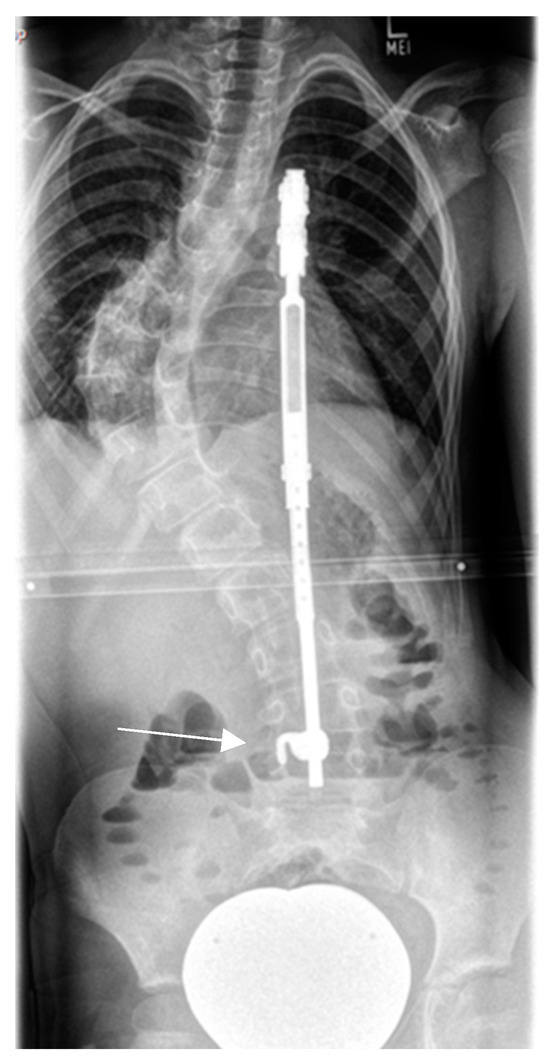

- Mladenov, K.V.; Spiro, A.S.; Krajewski, K.L.; Stücker, R.; Kunkel, P. Management of spinal deformities and tibial pseudarthrosis in children with neurofibromatosis type 1 (NF-1). Childs Nerv. Syst. 2020, 36, 2409–2425. [Google Scholar] [CrossRef]